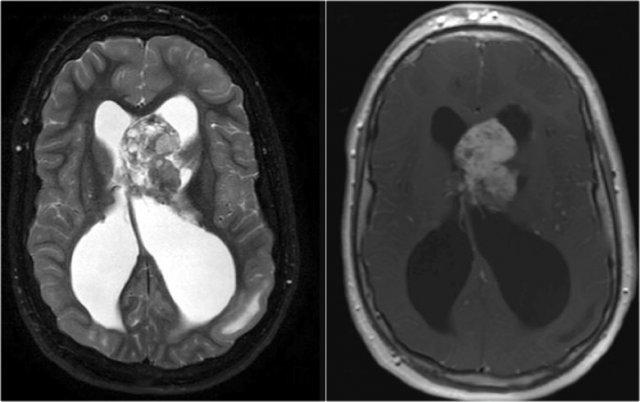

U tế bào hạch thần kinh đệm (Ganglioglioma) ở thùy chẩm phải biểu hiện dưới dạng khối nang với ngấm thuốc dạng viền. Lưu ý hình ảnh vôi hóa trên CT.

U tế bào hạch thần kinh đệm (Ganglioglioma)

Ganglioglioma là khối u thường gặp nhất liên quan đến động kinh thùy thái dương.

Vôi hóa là đặc điểm phổ biến của ganglioglioma và là yếu tố phân biệt quan trọng với DNET và u tế bào hình sao đa hình xanthochromic (pleomorphic xanthoastrocytoma).

Ganglioglioma ở một trẻ nhỏ. Lưu ý nang lớn với ngấm thuốc của mô đặc thành nang.

Ganglioglioma dạng nang nhỏ với nốt ngấm thuốc kích thước nhỏ.

DNET: Chuỗi xung T2W và FLAIR cho thấy hình ảnh bong bóng đặc trưng và phù nề các hồi não bị tổn thương. Lưu ý hình ảnh lõm xương sọ do khối u tăng trưởng chậm.

DNET

DNET trong các trường hợp điển hình biểu hiện dưới dạng khối dạng bong bóng làm giãn rộng các hồi não bị tổn thương.

Hình ảnh nang dạng bong bóng được thể hiện bởi các cấu trúc nhỏ giống nang trong khối u, tăng tín hiệu rõ rệt trên chuỗi xung T2W.

DNET ở bé trai 11 tuổi biểu hiện với cơn động kinh cục bộ kháng trị.

Khối u cho thấy hình ảnh dạng bong bóng đặc trưng và có hình ảnh lõm xương sọ kín đáo.